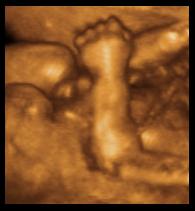

“Unfortunately, she says, her maternal instincts did not respond to reason: when a young friend placed her baby in her arms, she found herself looking with distaste into “a little scrunched face inspiring no tenderness, only intense tedium at the thought of tending him. What was I going to do with the baby I couldn’t return to his mother?” She arranged to have amniocentesis once they got to England, though she was not sure – despite her reservations – what it would cost her emotionally to have an abortion if something were wrong. When told she had as much chance of having a miscarriage from the amniocentesis as she did, at her age, of having a Down syndrome child, she hoped for the miscarriage: “That is until, lying on the table where the procedure was to take place, I saw the ultrasound scan on a television monitor above me reveal the perfectly shaped head of the child I carried. I wanted that baby!”